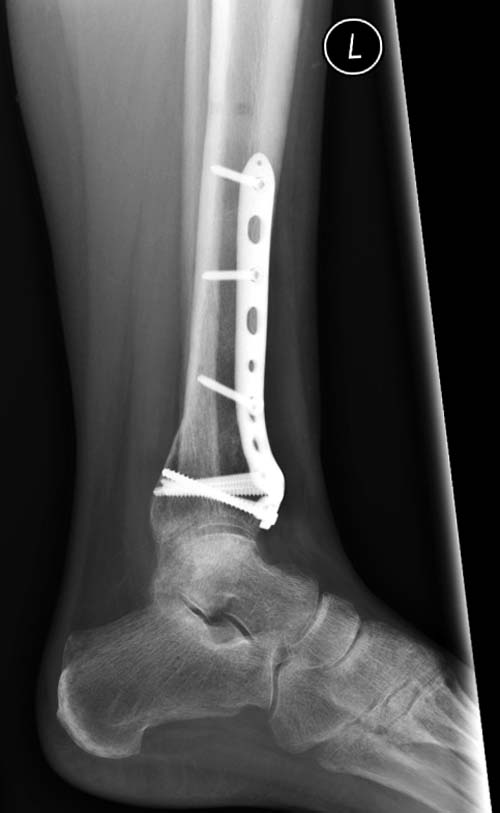

С ответом немного задержался, хотел подобрать материал, но трудно найти идентичный случай. На всякий случай подобрал пару, надеюсь, поможет.

Первый случай, где перелом в результате падения с небольшой высоты, где мортиз рентген снимок показал отстутствие укорочения наружной

лодыжки и КТ срезы подсказали направления атаки. После такой фиксации нет надобности в гипсовой повязке, брейс и через две недели движения в

суставе без нагрузки.

Второй случай в результате скоростной травмы, кроме пилона, вовлечение других органов! Отек при поступлении и открытый перелом на другой стороне. В таких случаях нет смысла спешить, и временный наружный фиксатор на несколько дней. После спадения отека фиксация передне-наружной пластиной. Реабилитация - ранние движения, без нагрузки.